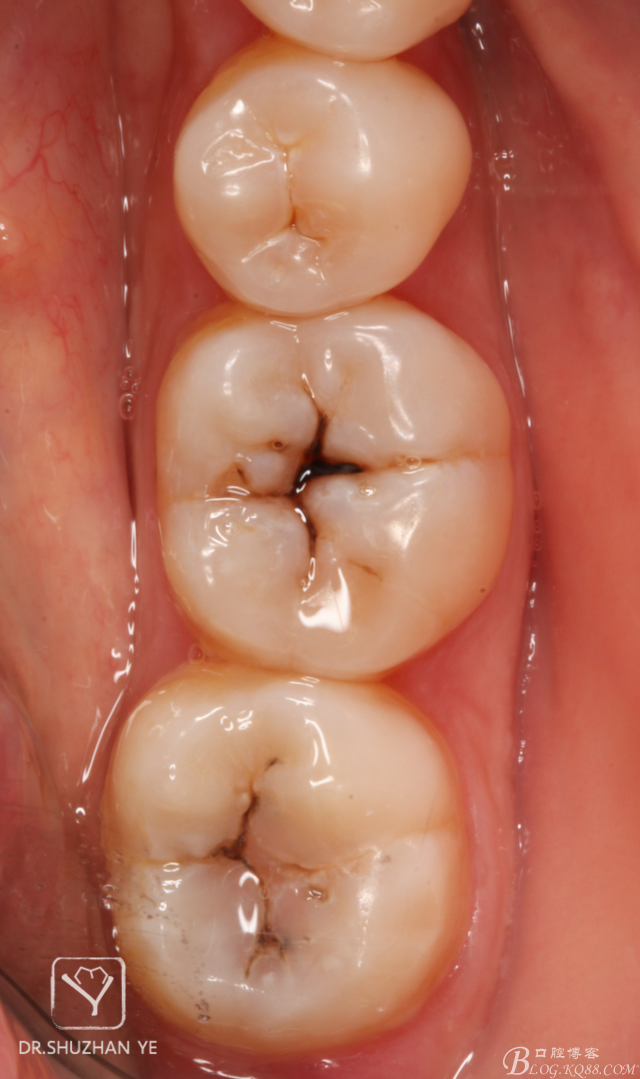

3、上橡皮障

9、術(shù)后即刻

20151205082652_68838.jpg

10、拆除橡皮障,初步調(diào)合,修整,拋光

20151205082703_48044.jpg